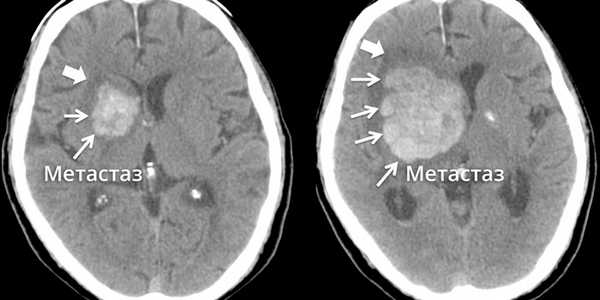

Метастазы головного мозга, фото. На КТ с контрастным усилением у пожилой пациентки (в верхнем ряду слева) с жалобами на головные боли выявлены множественные объемные образования в левом полушарии мозга, интенсивно накапливающие контрастное вещество. Образования имеют характерную форму в виде «кольца». На изображениях в нижнем ряду и вверху справа определяются множественные очаги в головном мозге: отчетливо видны округлые образования с более плотным «ободком» по периферии, располагающиеся в левой теменной доле.